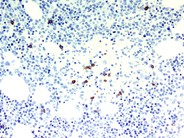

Гистоплазмоз и анкилостомидоз что это - фото презентация